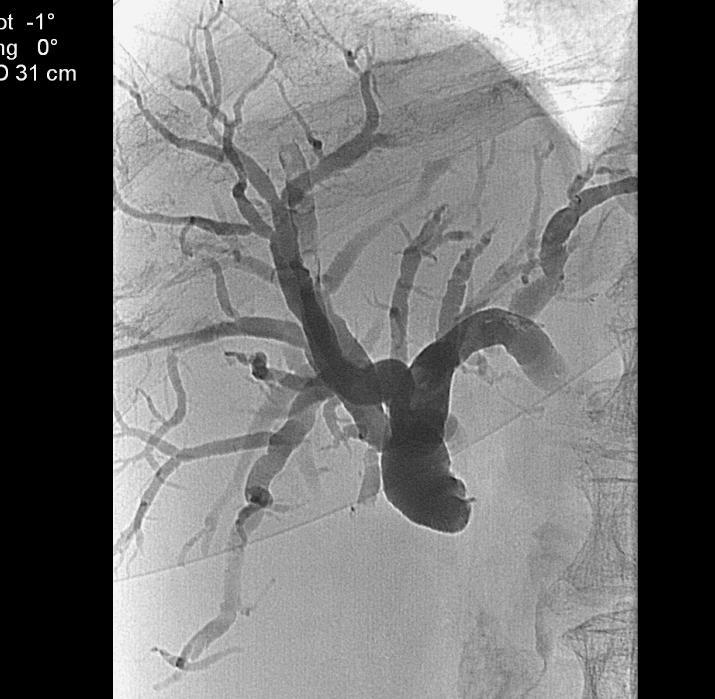

14.1.1.5. Angiography

The CT-angiography and MR-angiography methods take nowadays over from the diagnostic selective catether hepatic angiographies. The catheter angiographies are performed in case of therapeutic (TAE – Figure 7, TACE, chemoperfusion) interventions and the traumatic liver injuries (selective embolisation) on these fields.

Figure 7: TAE (Transarterial Embolisation) of the liver with Lipiodol

Concerning the HCC, the knowledge of history is very important for the decision and usually the oncoteams consider the performance of an imaging modality guided biopsy basically important for the further therapeutic decisions (because of the hystological validation rather core biopsy should be performed! (Figure 26, 27, 28).

Figure 27: HCC, TAE, agniography